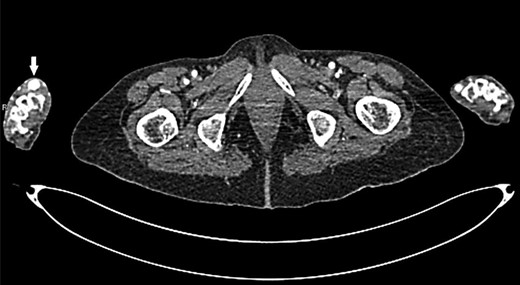

Upon physical examination, a mass of 2-by-3 cm found at the anatomical snuffbox area of the right hand, with no visible scars (Fig. 1). The mass was pulsatile, and no bruit was detected. The examination of the other arteries was negative. Later, CT angiography detected a local dilation at the distal part of the right radial artery (Figs 2 and 3). Complete body scan showed another aneurysm at the right common iliac artery measured 3-by-2.8 cm for which the patient was referred to a higher centre for possible endo-vascular intervention as it is not available in our hospital.

Transverse section of CT angiogram shows radial artery aneurysm at right hand (arrow).